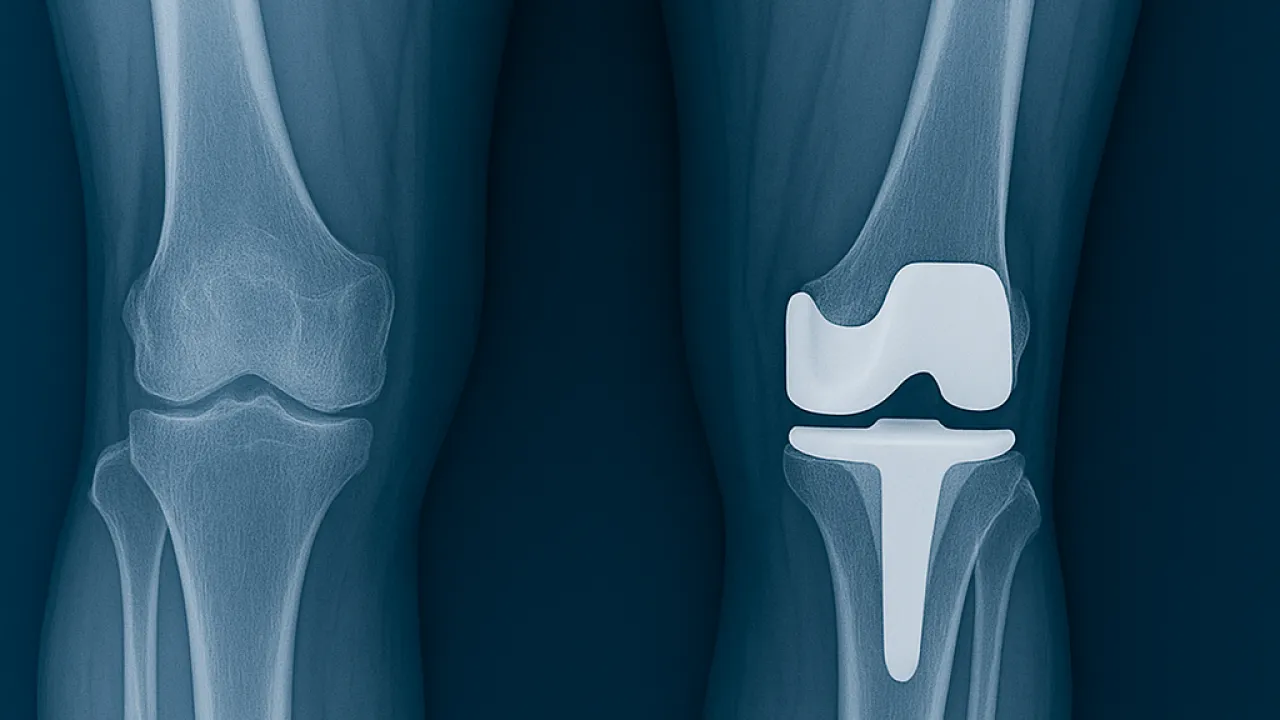

Diz kireçlenmesi (diz osteoartriti), eklem kıkırdağının aşınması sonucu ağrı, hareket kısıtlılığı ve yaşam kalitesinde ciddi düşüşe yol açar. İleri evrelerde en kalıcı çözüm diz protezi ameliyatıdır. Günümüzde protez cerrahisinde klasik yöntemlere ek olarak robotik diz cerrahisi de uygulanmaya başlanmıştır. Bu yöntem uzun yıllardır yurt dışında kullanılmaktadır. İzmir'de robotik diz cerrahisi yapan hekimlerden birisiyim. Deneyimim ise 2015 Yılında Fransa'nın LYON şehrinde Croix Rousse Hastanesi'nde çalıştığım sürede başladı. Burada gözlemci olarak değil, doktor olarak çalıştım. Bu sayede robotik diz cerrahisiyle tanışma fırsatım oldu. Her yöntem gibi artıları ve eksileri olan bu yöntemde de hasta seçimi ve uygun tedavi en önemli belirleyici unsurlardır.

Klasik Diz Protezi Ameliyatı

Klasik yöntemde cerrah, röntgen ve MR görüntülerini değerlendirerek ameliyat öncesi planlama yapar. Ameliyat sırasında ise bu plana dayanarak kemik kesilerini manuel olarak gerçekleştirir.

Robotik Diz Protezi Ameliyatı

Robotik cerrahi, ameliyat öncesinde 3 boyutlu görüntüleme teknolojileri kullanarak hastanın dizini sanal ortamda modellenmesini sağlar. Bu sayede protez yerleştirilmeden önce tüm ölçümler detaylı şekilde yapılır.

Ameliyat sırasında robotik sistem, cerrahın elini yönlendirir ve kemik kesilerini yüksek hassasiyetle gerçekleştirir.

Robotik ve Klasik Yöntem Arasındaki Fark

ÖzellikKlasik YöntemRobotik Yöntem

Planlama2D röntgen ile3D görüntüleme ve sanal modelleme

Cerrahi hassasiyetCerrahın el becerisine bağlıRobotik kol desteği ile milimetrik ölçüm

Protez ömrüStandartDaha uzun ömürlü

İyileşme süresiOrtalamaDaha hızlı

Kişiye özel uyumSınırlıMaksimum

Robotik diz protezi ameliyatı, klasik yönteme göre çok daha hassas, kişiye özel ve güvenilir bir teknolojidir. Cerrahın deneyimiyle birleştiğinde, hastalara ağrısız, hızlı ve uzun ömürlü bir çözüm sunar.